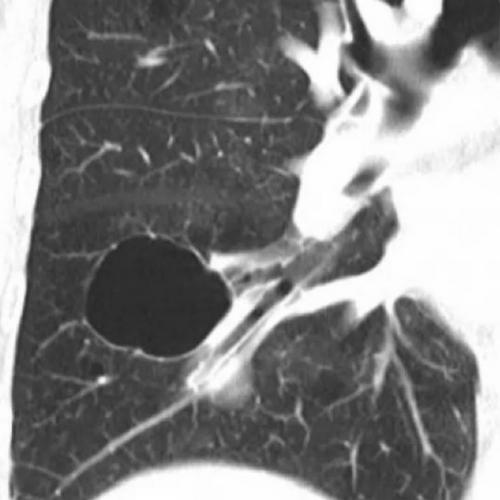

肺大泡,肺气肿,肺气囊,囊肿,空洞,ct如何鉴别?

如何区分"肺大疱","肺气囊","肺囊肿"

你报错了多少"肺气囊"?

肺气肿,肺大泡,肺气囊有什么不一样?